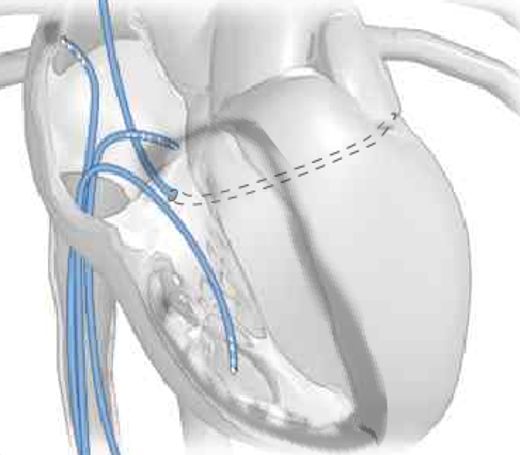

Effettua procedure di ablazione transcatetere e studi elettrofisiologici endocavitari per la diagnosi e il trattamento delle aritmie cardiache, esegue inoltre impianti di pacemaker, defibrillatori e dispositivi di resincronizzazione cardiaca per il trattamento dello scompenso cardiaco.